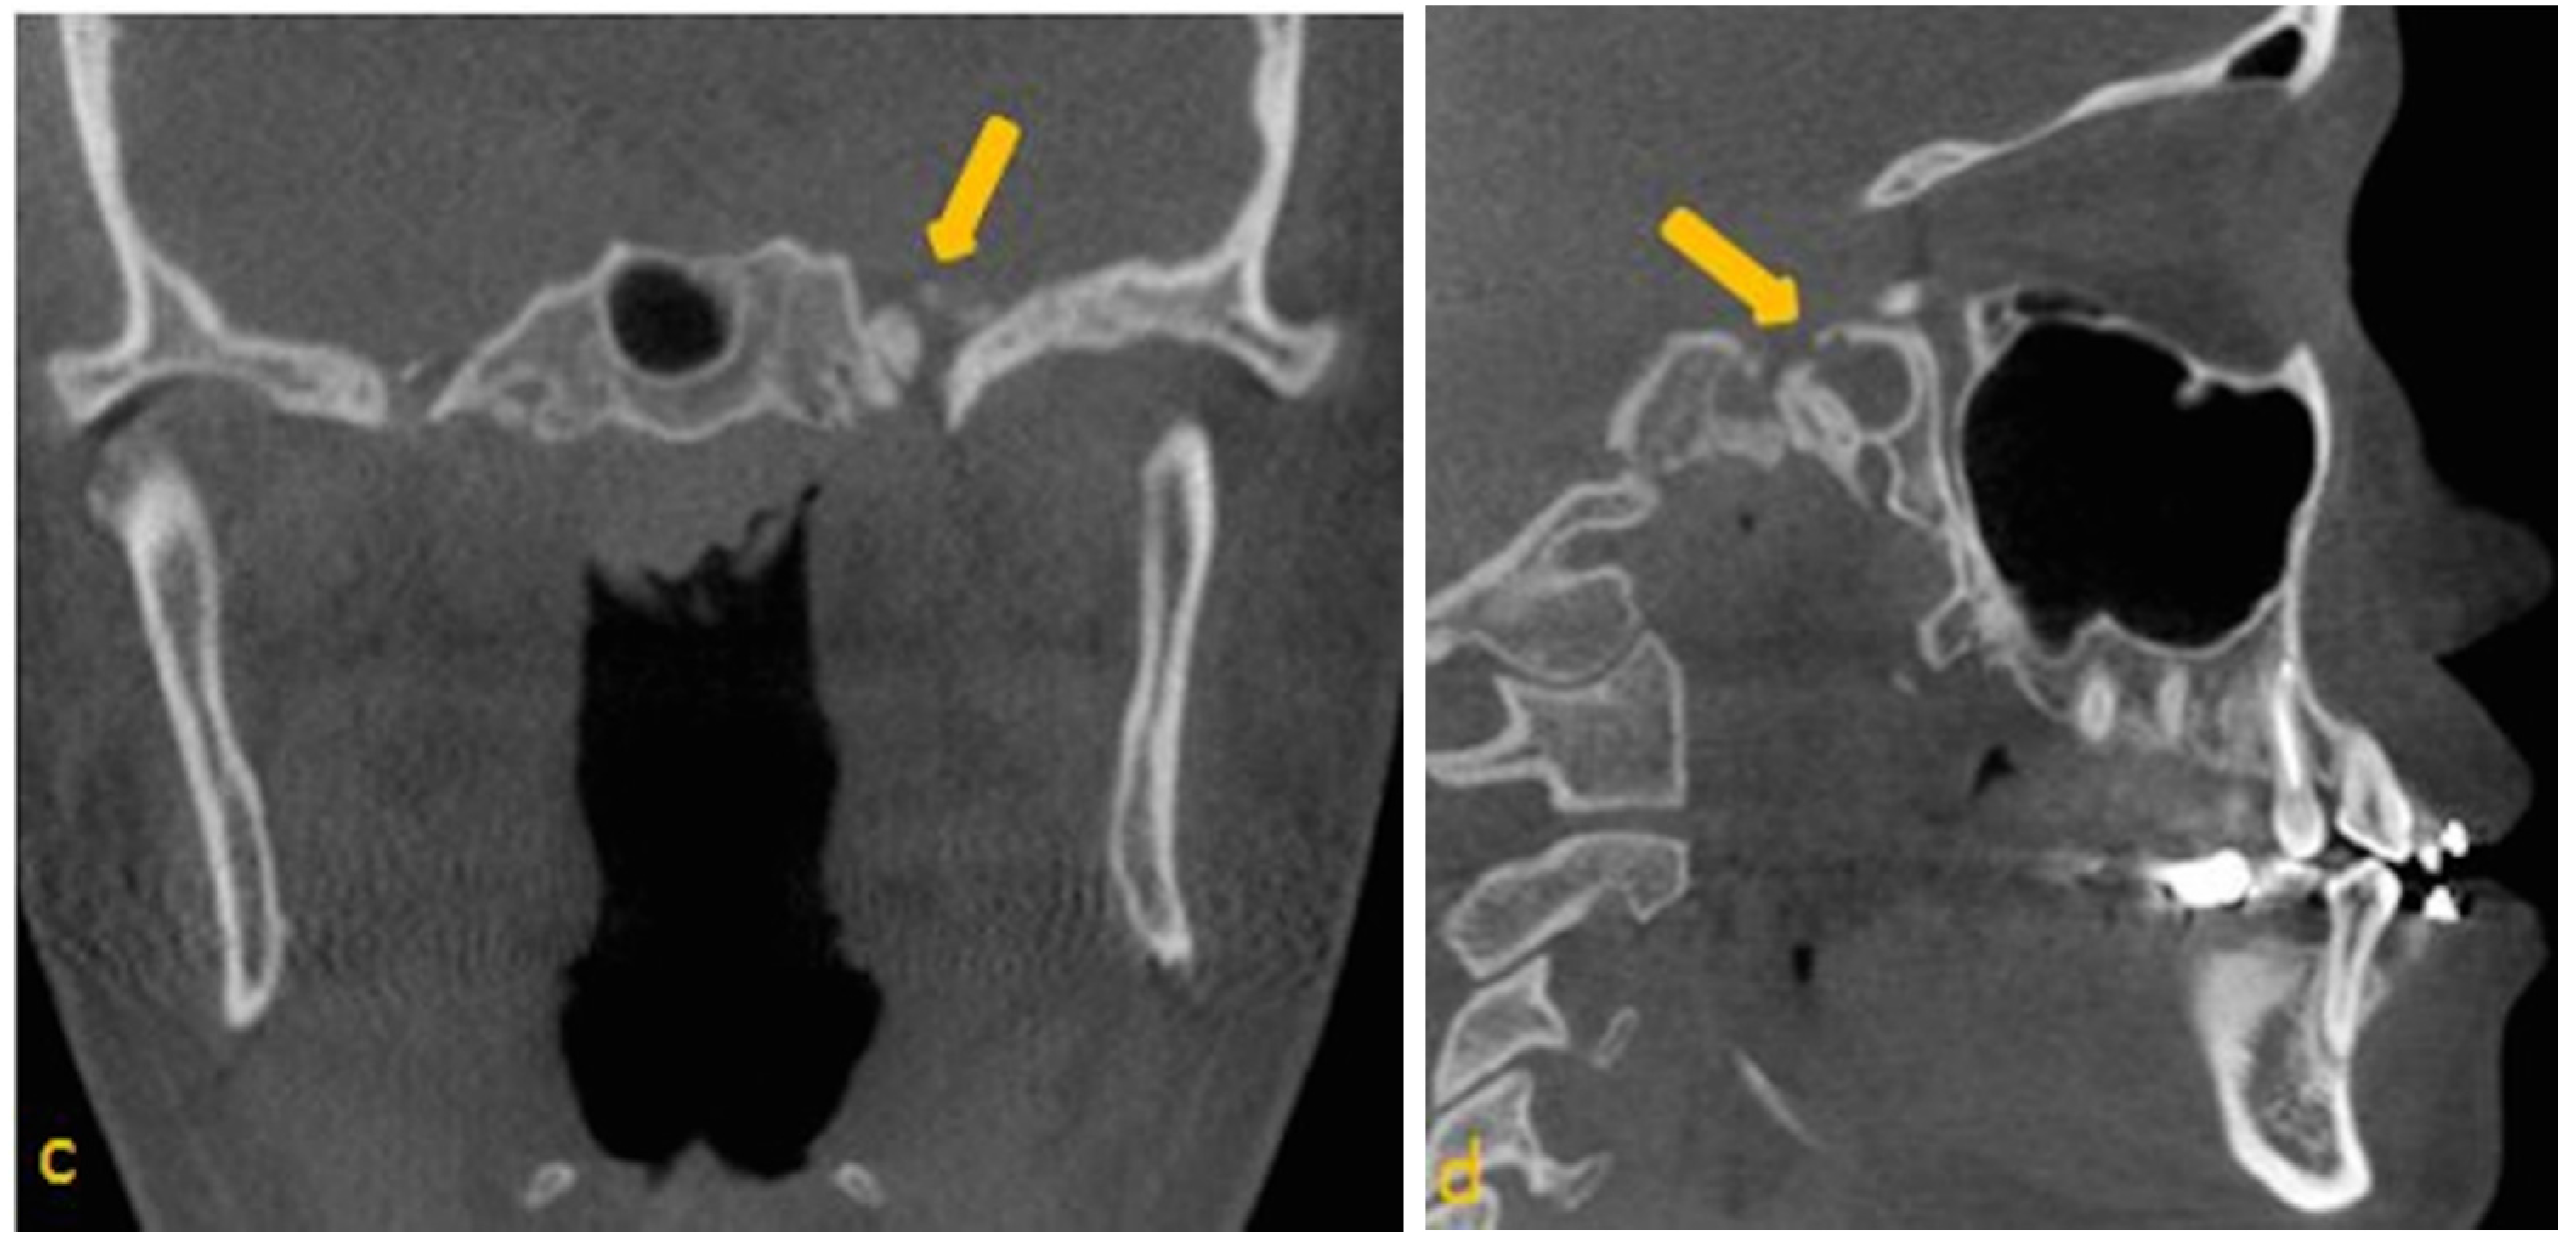

- Lesion must be non-expansile with sclerotic, well-defined margin, and should be located at a site of normal pneumatization. Evidence of fatty content should be present. Internal curvilinear calcifications should be noted on CT images [1].

- Since, sphenoid sinus is closely related to several vital neurovascular structures such as internal carotid artery and optic nerve, any associated skull-base foramina should remain intact and patent.